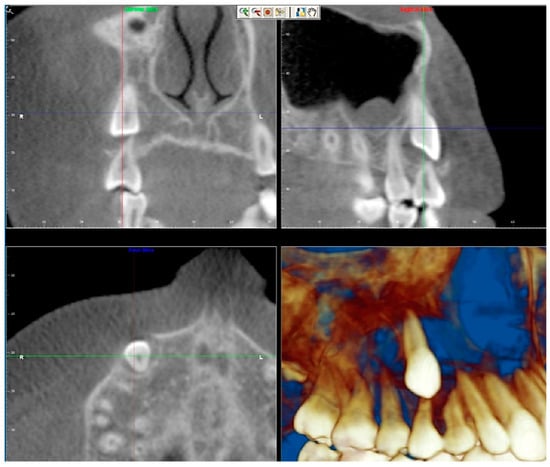

- Evaluation of buccal and lingual cortical plates: Figure 5, Figure 6 and Figure 7 show a case in which the mandibular lateral incisors are positioned lingual to the central incisors. Both mandibular lateral incisors are adjacent to each other. Figure 5 shows and intraoral occlusal photos with retained deciduous mandibular lateral incisors. There was no way to evaluate the buccal and lingual cortical plates through conventional 2D panoramic, periapical or occlusal radiographs. Therefore, CBCT was acquired and collimated to the area of teeth in order to assess the relationship of the four mandibular incisors to the labial and lingual cortical plates as well as to the adjacent teeth. As Figure 6 and Figure 7 display, CBCT shows that all permanent mandibular incisors are sound. It is important to note that thin buccal and lingual cortical plates may not be seen via CBCT—this does not denote that they are not present. In other words, CBCT images may not show a clinically present thin buccal and lingual cortical plates. In this case, the diagnostic information obtained from CBCT is far more significant than the information obtained from any other radiographic imaging technique.